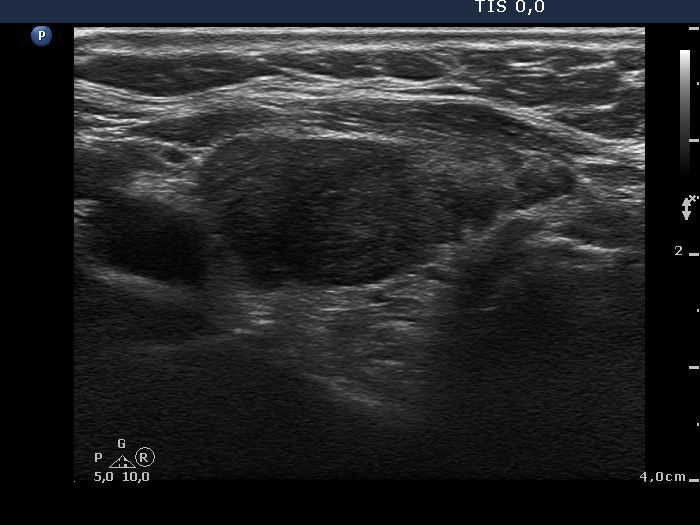

First examination - before surgery (first and second rows of images)

Clinical data: A 58-year-old woman with relapsing hyperthyroidism was managed by another team. She was sent for aspiration cytology. Multiple hypoechogenic nodules were described on ultrasonography.

Ultrasonography. Both lobes were hypoechogenic and contained several hypoechogenic areas do not corresponding to nodules. The echogenicity index was 20%. The vascularization was a bit increased.

Aspiration cytology was performed from one of the hypoechogenic areas in the right thyroid and resulted in benign, hormonal atypia.